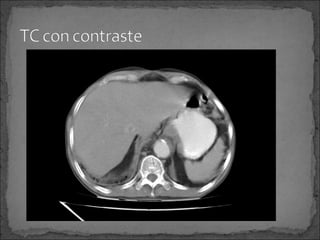

Paciente de 50 años de edad, con historia de Ca renal

diagnosticado hace 6 meses, quien súbitamente inicia

con dolor en cuadrante superior izquierdo hace 6 horas

por lo que consulta.

Facultativo le solicita una TC abdominal y luego refiere a

paciente a este centro hospitalario.

Paciente de 50años de edad, con historia de Ca renal diagnosticado hace 6 meses, quien súbitamente inicia con dolor en cuadrante superior izquierdo hace 6 horas por lo que consulta. Facultativo le solicita una TC abdominal y luego refiere a paciente a este centro hospitalario.